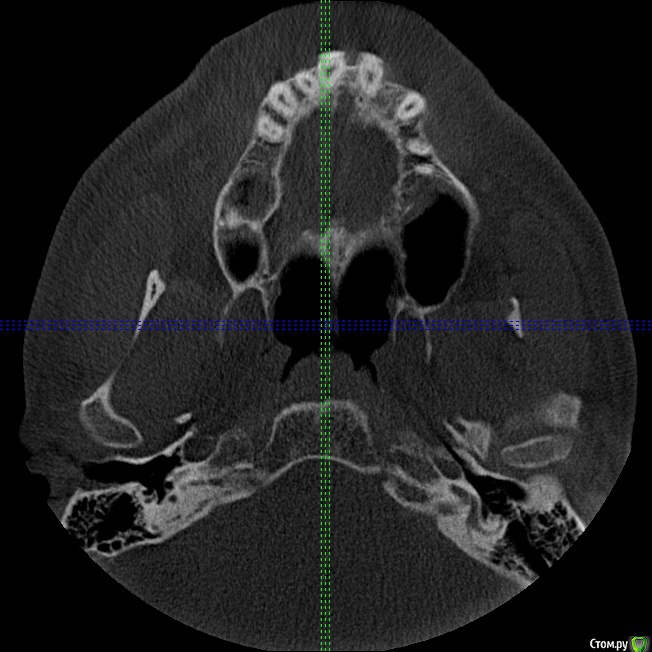

Секатор Опубликовано 4 октября, 2015 Поделиться Опубликовано 4 октября, 2015 (изменено) Здраствуйте,уже писал,но проблем много,но сча есть снимки зд(ссори за флуд).Начну издалека года два летом примерно неделю начили болеть зубы справа с отдованием в ухо и висок,оперативно ничего не делал(спас ал алкоголь),но я решил,что это 8-ки,и за зиму последнию все удалил,но отдования в висок и болезненность уха осталось,много времени прошло после удаления.Напряжение у виска и в области уха,взгляните на мою 6 справа,дно пазухи деформировано под её давлением,боли в области зуба нет-она причина?По лор все чисто,как будто болит зуб отдовая в ухо и висок,но без боли в области челюсти.Ближе к внутренней стенки пазухи и заходя на неё сформирован остроконечный конус дном пазухи,вследствии давлении корня зуба. Изменено 4 октября, 2015 пользователем Секатор 1 Ссылка на комментарий

Секатор Опубликовано 15 октября, 2015 Автор Поделиться Опубликовано 15 октября, 2015 (изменено) И,ещё раз прошу взглянуть смотрите,как деформирована внутреннеяя стенка пазухи зубом,у дна.Может корень подцепил,стенку пазухи? Изменено 15 октября, 2015 пользователем Секатор Ссылка на комментарий

kozloff Опубликовано 16 октября, 2015 Поделиться Опубликовано 16 октября, 2015 Поймите, с пазухой все хорошо, просто отлично, и с корнем верхнего зуба тоже. Удаляйте злосчастный мышьяк, пломбируйте каналы в пульпитом зубе и будет вам счастье! Ссылка на комментарий

IvanK Опубликовано 16 октября, 2015 Поделиться Опубликовано 16 октября, 2015 С пазухой все хорошо Меньше читайте про зубы и не надо постоянно смотреть свое кт... Хорошего дня) 1 Ссылка на комментарий